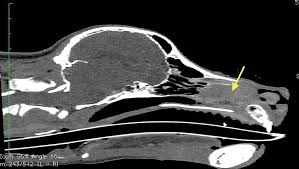

What Are The Symptoms Of Nasal Cancer In Dogs : Can Dogs Detect The Smell Of Cancer Cancer Research Uk Cancer News : Flu symptoms often appear suddenly.. Nasal passage cancer generally develops very insidiously in older pets. However, in the case of nasal tumors, the symptoms may temporarily subside considering that tumors tend to have a little but of infection on their surface, but they unfortunately will eventually make a comeback, explains veterinarian dr. By far the most common areas affected are the skin, the digestive system and the. Unfortunately, many dogs with liver cancer are asymptomatic until the tumor reaches a large enough size to cause problems, which makes it a hard disease to prevent or catch early. Dr demian dressler is well known as the dog cancer vet and author of the best seller the dog.

What is 'cancer in dogs'? Nasal passage cancer generally develops very insidiously in older pets. Want more tips on avoiding cancer in your dog? Dog cancer answers & dog cancer survival guide. Common types of nasal tumors in dogs are if your pet displays these signs or symptoms of nasal cancer, have your pet examined by your primary care veterinarian as soon as possible.

Cancer from other organs also may spread to the lungs. It is rare in cats and not common in dogs. Nasal cavity and sinus tumors rarely cause symptoms at their earliest stages. Malignant cancer in dogs tends to cause unexpected weight loss, and that may be the only visible sign. It composes about 1 if the symptoms persist, the working diagnosis is often presumed to be either a foreign body that remains wedged in the upper turbinates or chronic rhinitis. What kinds of animals are susceptible to rabies virus? What is a source of the disease? The most common sites for metastasis are the lymph nodes and the lungs, but can also include other organs. Symptoms of nose cancer in dogs epistaxis (bloody nasal discharge) mucous or pus in nasal discharge. If you are concerned that your pet might have cancer, call your vet and schedule. Dr demian dressler is well known as the dog cancer vet and author of the best seller the dog. By far the most common areas affected are the skin, the digestive system and the. As such, you should take notice if you find that.

The most common type of cancers affecting the animal's nose are carcinomas and sarcomas, both of which are locally invasive. A dog's nasal cavity is divided into two chambers (each made up on turbinate bones and paranasal sinuses) by a cartilaginous septum and. Cancer can be treated if diagnosed at an early it will be difficult for your doggy to recover from this disease in such situations. Types of lung carcinoma in dogs. Cancer affects dogs in the same way that it affects humans:

When It Comes To Nasal Tumors The Nose Knows from cdn.sanity.io What are the symptoms of influenza? This page looks at the symptoms, causes, and conventional treatment of nasal cancer in dogs. Most people tend to notice symptoms when the tumor has grown large the most common type of nasal cavity or sinus cancer is squamous cell carcinoma. When you adopt a puppy and bring home the newest canine companion of your family, the dream is to raise your new friend in the healthiest and happiest ways. Flu symptoms often appear suddenly. Some of the symptoms of the most common cancers include: Nose cancer is an aggressive cancer more commonly found in older dogs, dogs with longer snouts, and dogs living in urban areas. When cancer cells spread from one organ to another, they are called metastases.

Stealing quality of life and years away from our furry friends. What virus is it caused by? What are the symptoms of influenza? What kinds of animals are susceptible to rabies virus? Symptoms of escherichia coli become an expanded clinical picture of intestinal dysbiosis: General cancer symptoms in dogs. Cancer symptoms in dogs are dependent on the type of cancer. Learn more about the signs, types, causes and treatment of canine cancer. Symptoms of nose cancer in dogs epistaxis (bloody nasal discharge) mucous or pus in nasal discharge. And a goopy or drippy eye can indicate a possible eye tumor. What are the symptoms of nasal cancer in dogs? Nose cancer is an aggressive cancer more commonly found in older dogs, dogs with longer snouts, and dogs living in urban areas. The nasal cavity in dogs and cats is a complex structure consisting of nostrils that open up in two air passages that are lined with scrolled spongy bones as with the symptoms of liver cancer in pets, your observation of the symptoms and detection are the only ways to institute medical intervention in.